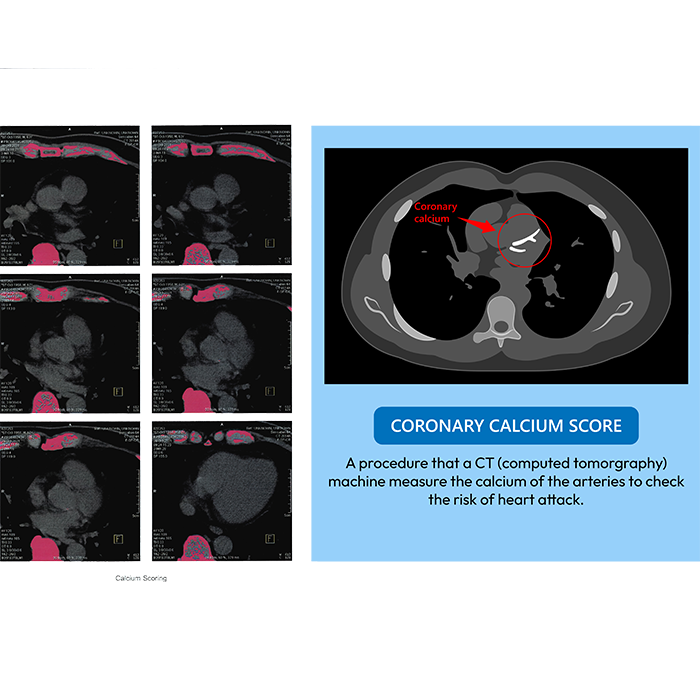

Coronary Calcium Score

A coronary calcium CT scan, also known as a heart scan, is a non-invasive imaging test that uses a computed tomography (CT) scanner to detect calcium deposits in the coronary arteries. These deposits, known as plaque, can narrow the arteries and increase the risk of heart disease.

It is used to evaluate a patient's risk for coronary artery disease (CAD) by detecting calcified plaque in the arteries, especially for asymptomatic individuals with intermediate risk factors like high cholesterol, high blood pressure, diabetes, a family history of early heart disease, or a history of smoking. The scan produces a Coronary Artery Calcium (CAC) score, which helps predict future heart attacks and informs treatment decisions. A doctor may recommend a coronary CT scan if you have symptoms of heart disease, such as recurring chest pain or shortness of breath, or to evaluate risk factors like a family history of heart disease, high cholesterol, or diabetes.

- Provides a Calcium Score: A coronary calcium scan measures calcium deposits in the arteries, providing a score that indicates your risk for heart disease.

- The images are analyzed to calculate a calcium score, which indicates the amount of calcium buildup.